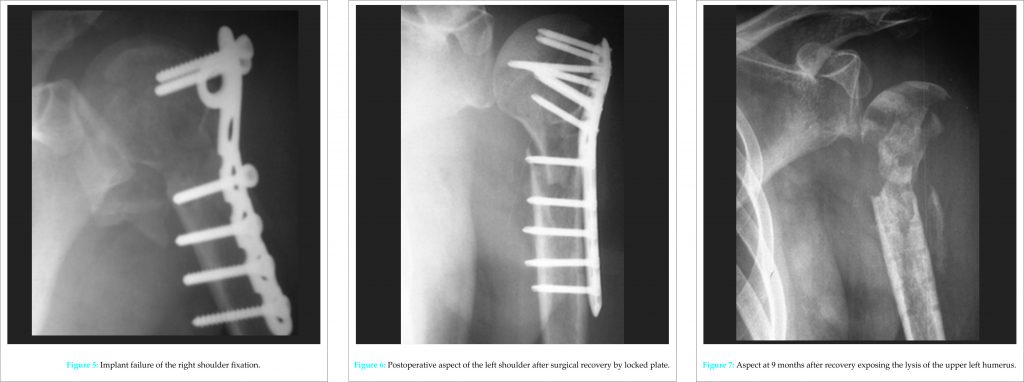

The CT scan has detailed bone lesions (Fig. 3). There was no notion of falling during or after these convulsions. The following day, the traumatic lesions were reduced by external maneuvers for the right shoulder (Fig. 4) and open reduction and internal fixation by anatomical plate of left shoulder lesions through a transdeltoid longitudinal approach. The two shoulders were immobilized complementarily by removable splints arm to the body. In the immediate aftermath of surgery, he presented episodes of agitation which led to the dismantling of the left shoulder internal fixation (Fig. 5). The improvement of its neurological state and of the biological markers toward the 15th day allowed a reprise of the left shoulder with contribution of graft and a fixation of the major tubercle on the right.

At the request of his entourage, he was evacuated to the North Country where an ablation of the left shoulder material and stabilization by locked plate were carried out (Fig. 6). The sequelae were marked by the occurrence of an osteomyelitis with osteolysis of the entire upper right humerus extremity (Fig. 7). It will require an inverted prosthesis.